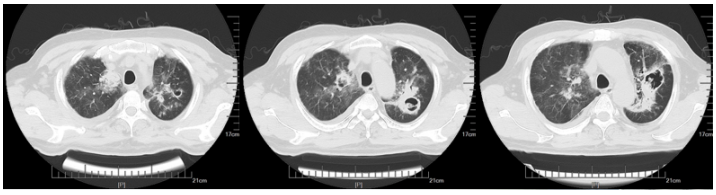

现病史:患者2024年1月7日左右无明显诱因下出现鼻塞等,外院胸部CT示:两肺炎症,肝内多发低密度灶。1月18日胸部CT:两肺散在渗出、斑点及空洞(图11)。当地医院予哌拉西林他唑巴坦抗感染,1月20日住院期间发热,热峰37.6℃,1月23日发热,热峰39℃,更换抗生素为头孢哌酮舒巴坦+左氧氟沙星,患者仍反复发热,1月25日达热峰38.4℃。

图11  患者胸部CT(2024-01-18)

1月31日复查胸部CT提示病灶进展,出现团块及空洞样改变(图12)

图12  患者复查胸部CT(2024-01-31)

2月9日再次复查胸部CT可见肺部弥漫及多发病灶较前吸收(图13)。患者症状改善,体温恢复正常,遂予出院,序贯艾沙康唑胶囊200 mg qd。

图13  患者复查胸部CT(2024-02-09)

3月16日门诊随访胸部CT: 双肺实变基本吸收, 右上肺仅余空洞、纤维条索样病灶(图14)

图14  门诊随访胸部CT(2024-03-16)